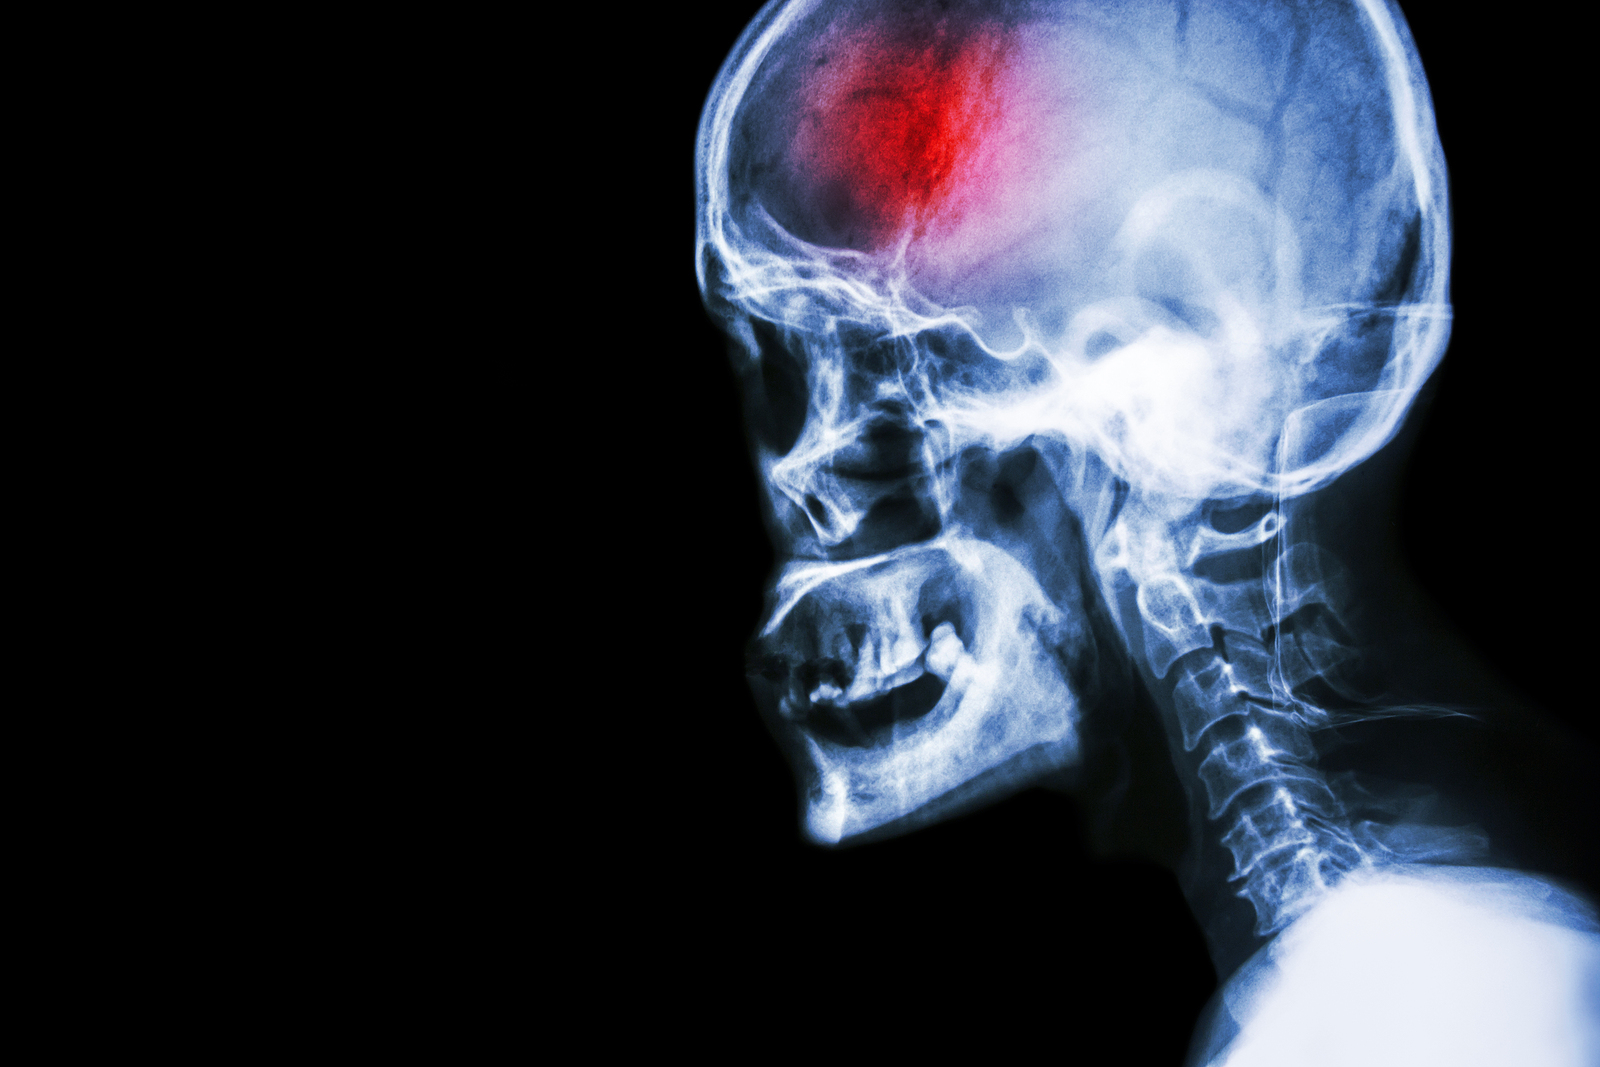

Diagnosis

The classic signs and symptoms of a stroke often create an obvious suspicion of stroke, however once at a medical centre, other objective tests are completed to confirm the stroke diagnosis. It is important for the medical team to determine which kind of stroke is occurring in order to assist with the most effective type of treatment.

Physical Examination: A physical exam to assess the function of your limbs, face, and mental capacity will be completed. In addition, your heart rate and blood pressure will be taken.

Blood Tests

Blood tests are completed to look for markers in your blood such as cholesterol, signs of infection, blood sugars, and the ability for your blood to clot.

Computed Tomography (CT) scan and/or Magnetic Resonance Imaging (MRI) scan: These tests are done on your brain and used to locate the exact location of the stroke and to determine if it has been caused by a blockage or a bleed. These tests can also help rule out other conditions that may be causing symptoms, such as an infection or a brain tumour

Other tests

Several other tests may be conducted to assist in diagnosing a stroke, such as echocardiograms to look at the heart, or ultrasounds to check for the state of the carotid arteries in your neck.